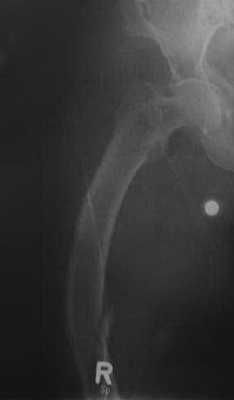

Взрослая форма несовершенного остеогенеза у женщины 63 лет. Рентгенологическое исследование правой бедренной кости. Увеличение рентгенопрозрачности в сочетании с остеопорозом. Варусная деформация бедренной кости. Переломы в средней части диафиза бедренной кости после минимальной травмы.